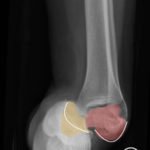

The X-rays were significant for a subtalar dislocation. The calcaneus (red) is laterally displaced with respect to the talar head (orange), and the white lines indicate the normal articular surface. Additionally, there was a talonavicular dislocation, as seen in the fourth image: the talus (green) and navicular bone (purple) overlapping suggests a dislocation. In a normally aligned foot, the boundaries of the two bones create a point of articulation.